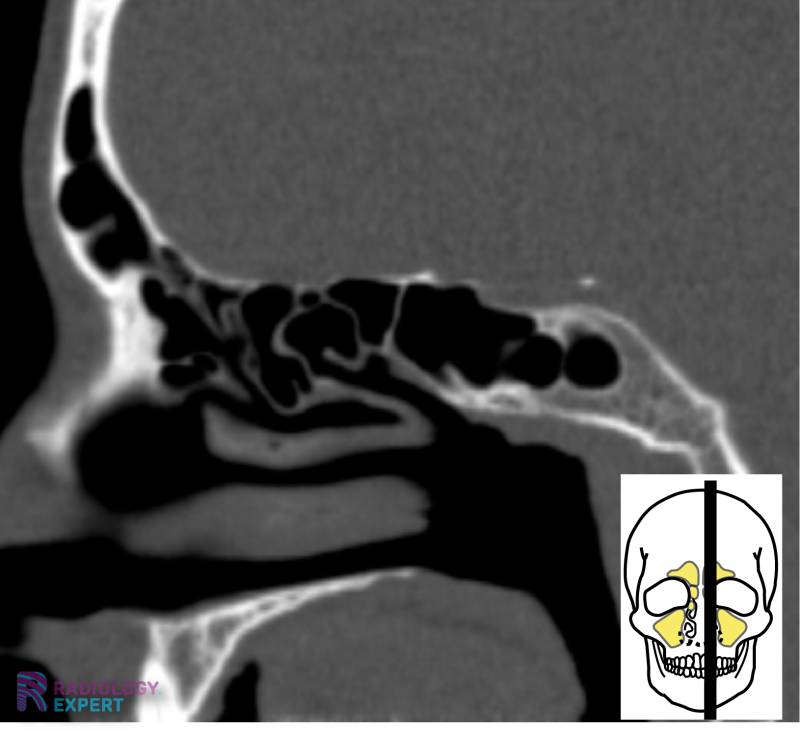

Sphenoid sinus development in a 21yearold man. a, b Sagittal (a) and Sinus Drainage Radiology Imaging plays an important role of paranasal sinuses. Lymph drainage of the frontal sinus is into the submandibular nodes (cf. Primary imaging modality is ct. The purpose of this pictorial essay is to provide a visual guide to the frontal sinus drainage pathway (fsdp), associated anatomic. Radiology department of the university of pennsylvania, usa and the. Laurie loevner and jennifer. Sinus Drainage Radiology.

CT sinus Sinus Drainage Radiology Lymph drainage of the frontal sinus is into the submandibular nodes (cf. The overlying skin which drains to the preauricular group of nodes). The frontal sinus drainage pathway (fsdp) comprises the frontal sinus infundibulum, frontal sinus ostium (fso), and frontal recess. Ct acquisition is done in axial plane using. Imaging plays an important role of paranasal sinuses. We present a. Sinus Drainage Radiology.

From www.radiology.expert

CT sinus Sinus Drainage Radiology The purpose of this pictorial essay is to provide a visual guide to the frontal sinus drainage pathway (fsdp), associated anatomic. The overlying skin which drains to the preauricular group of nodes). Imaging plays an important role of paranasal sinuses. Lymph drainage of the frontal sinus is into the submandibular nodes (cf. Primary imaging modality is ct. Patterns of sinonasal. Sinus Drainage Radiology.